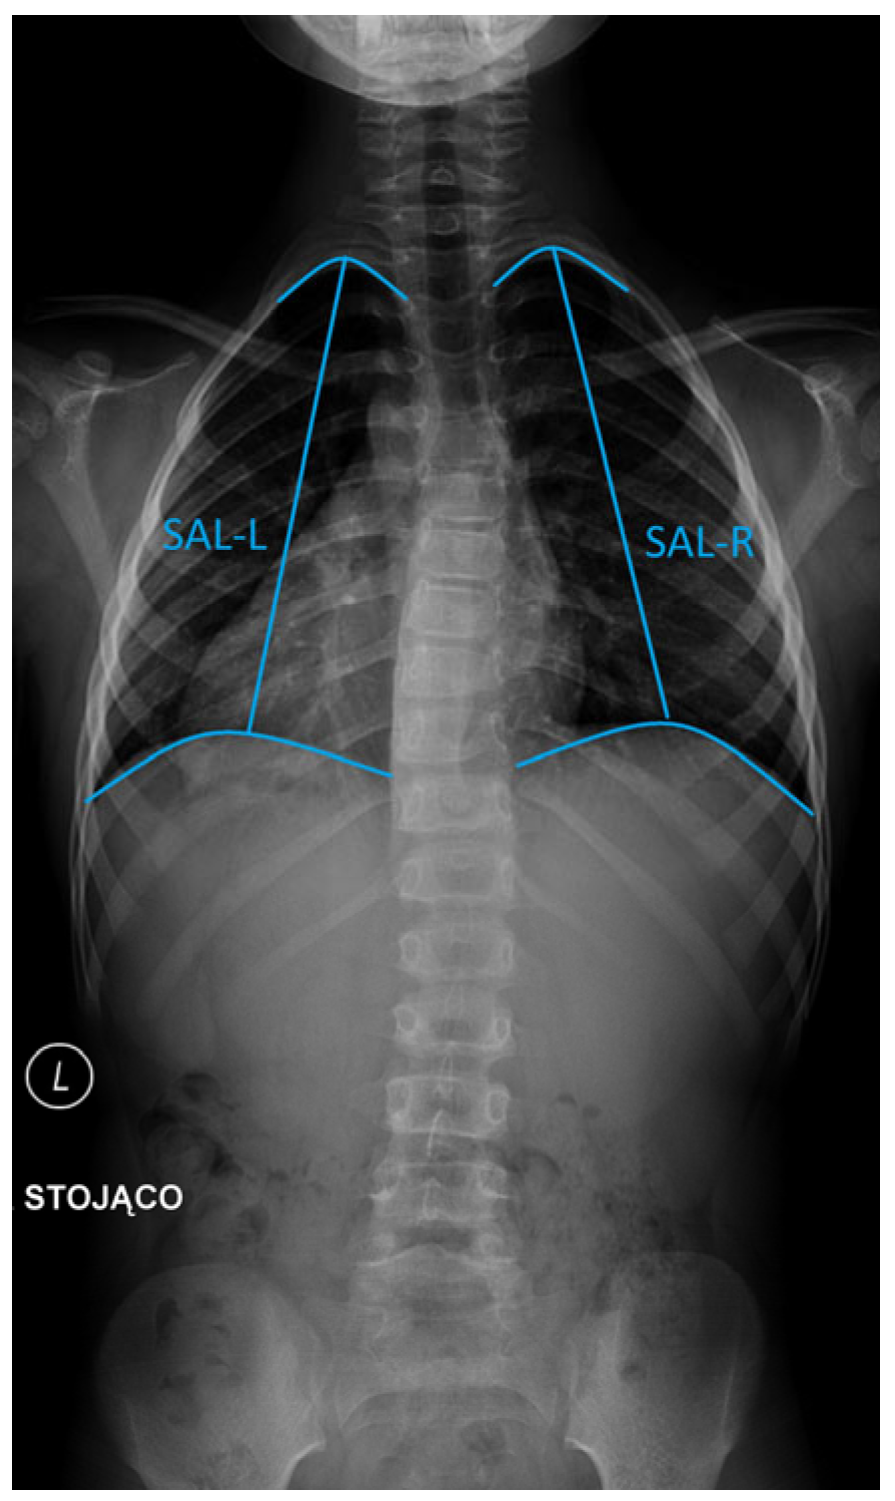

- Space available for lung (SAL) on the left (SAL-L) and right (SAL-R) hemithorax (cm): Determined separately for each hemithorax as the vertical distance from the midpoint of the most cephalad rib to the center of the ipsilateral hemidiaphragm [13] (Figure 3).

Figure 3. Measurements used in the manuscript: space available for lung (SAL) on the left (SAL-L) and right (SAL-R) hemithorax.